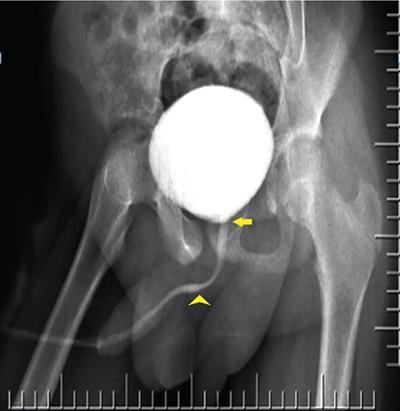

Image

Fig. 10.6.9 Normal appearance of a male urethra on an MCU. Yellow arrow points towards the prostatic urethra. The bulbar portion is marked by the arrowhead. Between the two lies the membranous urethra and distal to the bulbar urethra lies the penile urethra.